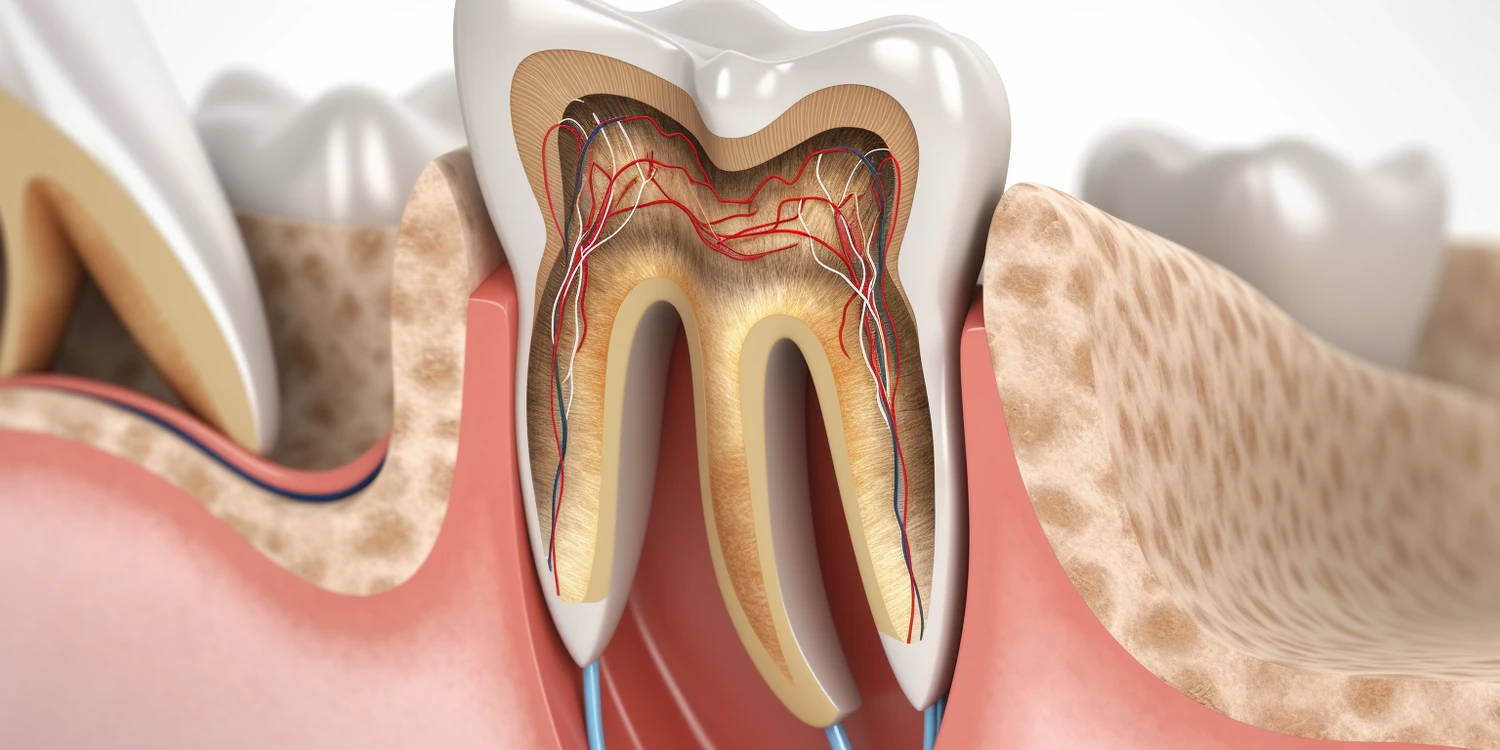

Leczenie kanałowe składa się z kilku kluczowych etapów, które mają na celu skuteczne usunięcie zakażonej tkanki oraz zabezpieczenie zęba przed dalszymi problemami. Pierwszym krokiem jest dokładna diagnostyka, która obejmuje zdjęcia rentgenowskie oraz ocenę stanu zęba. Ten etap może zająć od 30 do 60 minut. Następnie stomatolog przystępuje do znieczulenia pacjenta i otwarcia komory zęba, co również zajmuje około 30 minut. Kolejnym krokiem jest usunięcie miazgi oraz oczyszczenie i opracowanie kanałów korzeniowych. To najważniejsza część zabiegu i może trwać od jednej do kilku godzin w zależności od liczby kanałów oraz stopnia skomplikowania. Po zakończeniu oczyszczania lekarz wypełnia kanały materiałem uszczelniającym i zamyka komorę zęba.

W ostatnich latach rozwój technologii w dziedzinie stomatologii, a szczególnie endodoncji, znacząco wpłynął na efektywność i komfort leczenia kanałowego. Jednym z najważniejszych osiągnięć jest zastosowanie mikroskopów operacyjnych, które pozwalają stomatologom na dokładne zobrazowanie wnętrza zęba oraz precyzyjne opracowanie kanałów korzeniowych. Dzięki temu możliwe jest skuteczniejsze usunięcie zakażonej miazgi oraz minimalizacja ryzyka uszkodzenia zdrowych tkanek. Inną nowoczesną technologią są systemy rotacyjne do opracowywania kanałów, które znacznie przyspieszają proces leczenia i poprawiają jego jakość. Dodatkowo, zastosowanie materiałów biokompatybilnych do wypełniania kanałów korzeniowych zwiększa szanse na długotrwałe powodzenie zabiegu. Warto również wspomnieć o cyfrowym obrazowaniu, które umożliwia szybsze i dokładniejsze diagnozowanie problemów stomatologicznych.